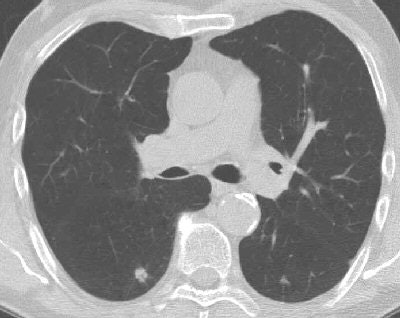

| CT image from ELCAP study shows right lower-lobe lung cancer. Image courtesy of Dr. Claudia Henschke. |

In addition, the report noted that the protocol specified the diagnostic workup following a positive result from the initial low-dose CT scan with the identification of noncalcified nodules. Henschke wrote that the workup "remained essentially unchanged in its indications for biopsy," as CT demonstrated growth of noncalcified nodules and the potential need for biopsy.

In this latest round of screenings, helical low-dose CT helped to diagnose lung cancer in 111 of the 6,296 women and 93 of the 8,139 men. When diagnosed with lung cancer, the research found that the men and women were almost the same age (68 years for the men, 67 years for the women), but women smoked less. The women smoked 47 pack years, compared with 64 pack years for the men.